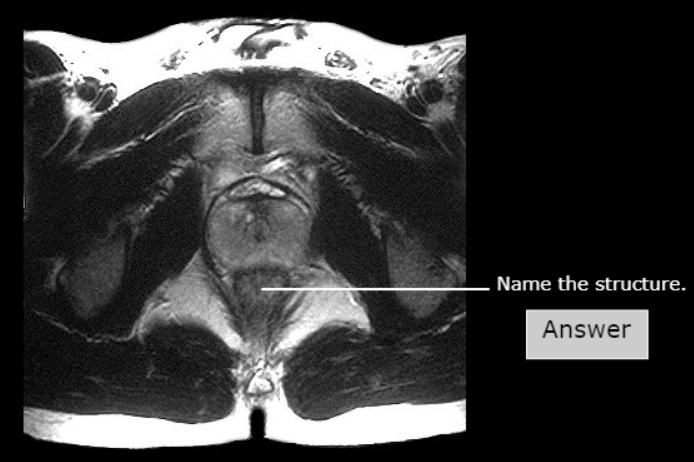

Levator ani